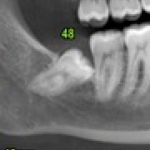

La presenza di questi segni richiede un controllo specialistico parodontale che dovrà essere effettuato, meglio se da un parodontologo, con l’ausilio di un set di 16 radiografie endorali.

L’esame parodontale, cioè il sondaggio, il controllo delle forcazioni, la mobilità, la presenza di tasche o di recessioni, verrà raffrontato ai dati radiografici precedentemente rilevati per una ulteriore conferma o meno della patologia presente.